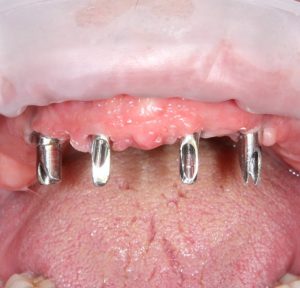

Именно поэтому к широко рекламируемым методам «всё-на-четырёх» или All-On-4 нужно относиться крайне осторожно — иногда лучше решать такие клинические задачи не быстро и за один раз, а в несколько этапов, последовательно и безопасно.

Реставрация фронтальной группы зубов.

Имплантация — Станислав Васильев       Протезирование — Давид Ахинян